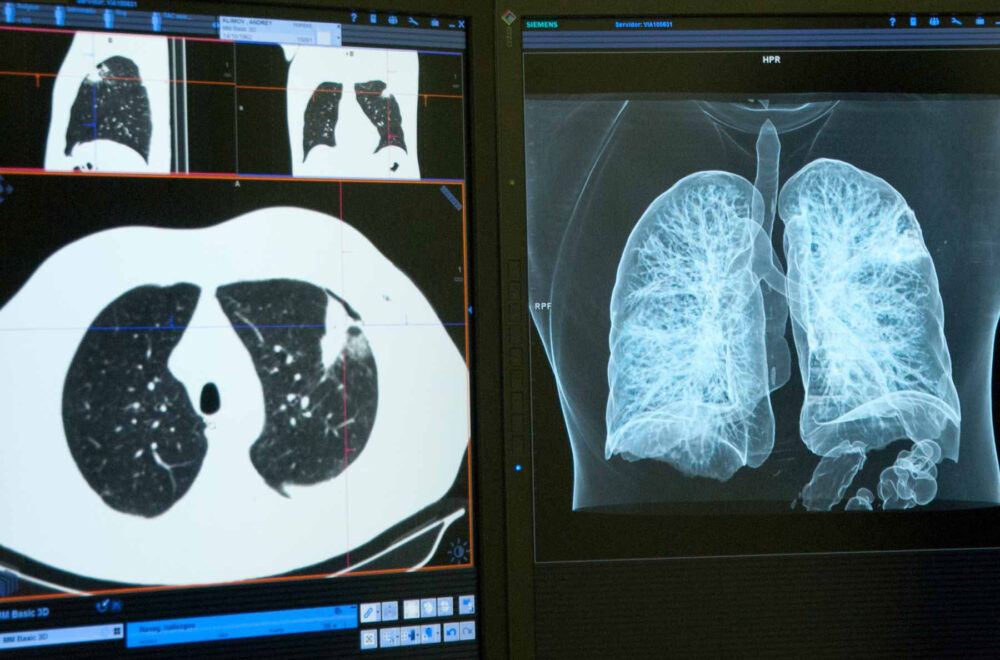

A CT or computerised tomography scan provides images of the body in slices or sections, from different angles, which are then reconstructed by a computer system to obtain a larger, more detailed 3-dimensional image.

A chest and abdominal CT scan can evaluate lung cancer and identify whether it has spread to regional (nearby) lymph nodes and whether there are any distant metastases.